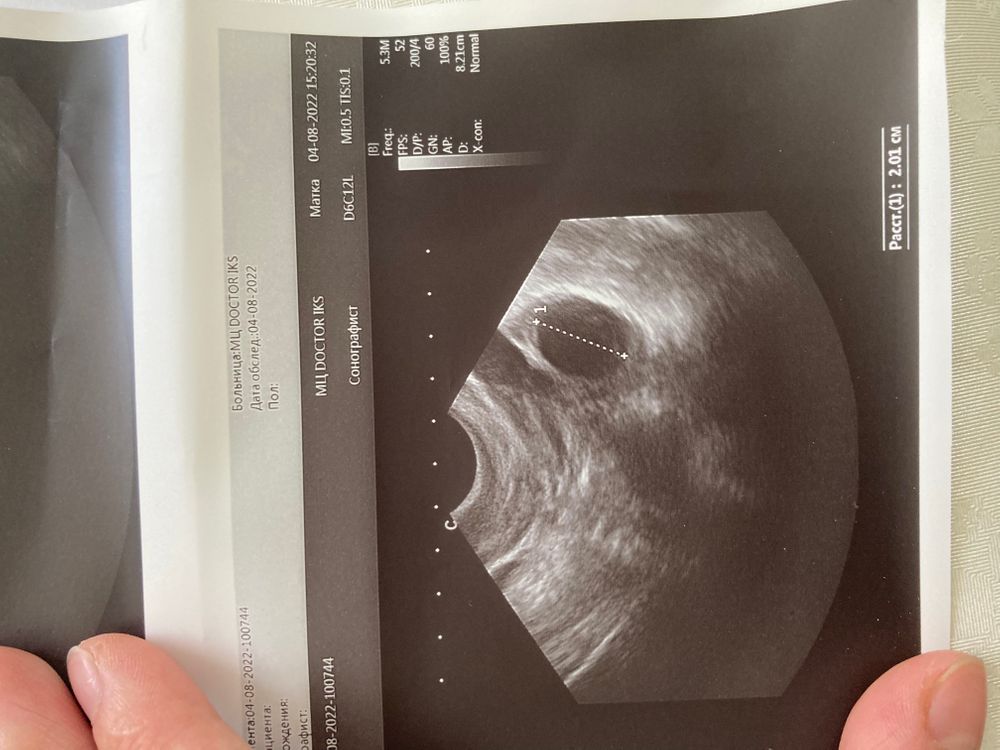

Что это?узи фолликулометрия

Доминантный фолликул ?Желтое. Тело?или Киста ?есть малое количество жидкости позади матки еще(незначительное)

Это фолликул. Какой размер намерили? Это точно не Желтое тело тк желтое тело с перегородками

Ну пока просто нелопнувший фолликул , будет размером ближе к 30 и без перспективы к овуляции то будет киста , на жт не похоже